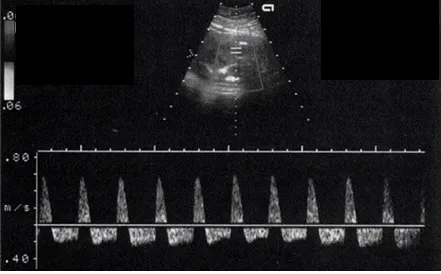

임신 36주에 접어든 28세 초산모가 태동 감소를 호소하며 내원했다. 혈압은 142/90mmHg, 맥박은 82회/분, 호흡은 20회/분, 체온은 36.7℃로 측정되었다. 초음파 검사 결과, 태아는 두위로 위치하고 있으며 예측 태아 몸무게는 1,700g (3백분위수)으로 나타났고, 양수지수는 5.5cm로 측정되었다. 골반 검사에서는 자궁경부가 닫혀 있으며, 소실은 관찰되지 않았다. 비수축검사와 탯줄동맥도플러검사 결과이다. 가장 적절한 처치 방법은 무엇인가?

[탯줄동맥도플러검사]

• 태동 감소로 내원한 산모에서 예측태아몸무게<10백분위가 확인되므로 FGR이 있다고 추정할 수 있으며, umbilical US상 reversed end-diastolic flow가 관찰된다. 이는 placental insufficiency를 의미한다.

• FGR이 있는 34주 이상의 태아에서 reversed end-diastolic flow가 관찰되므로 분만의 적응증이다.